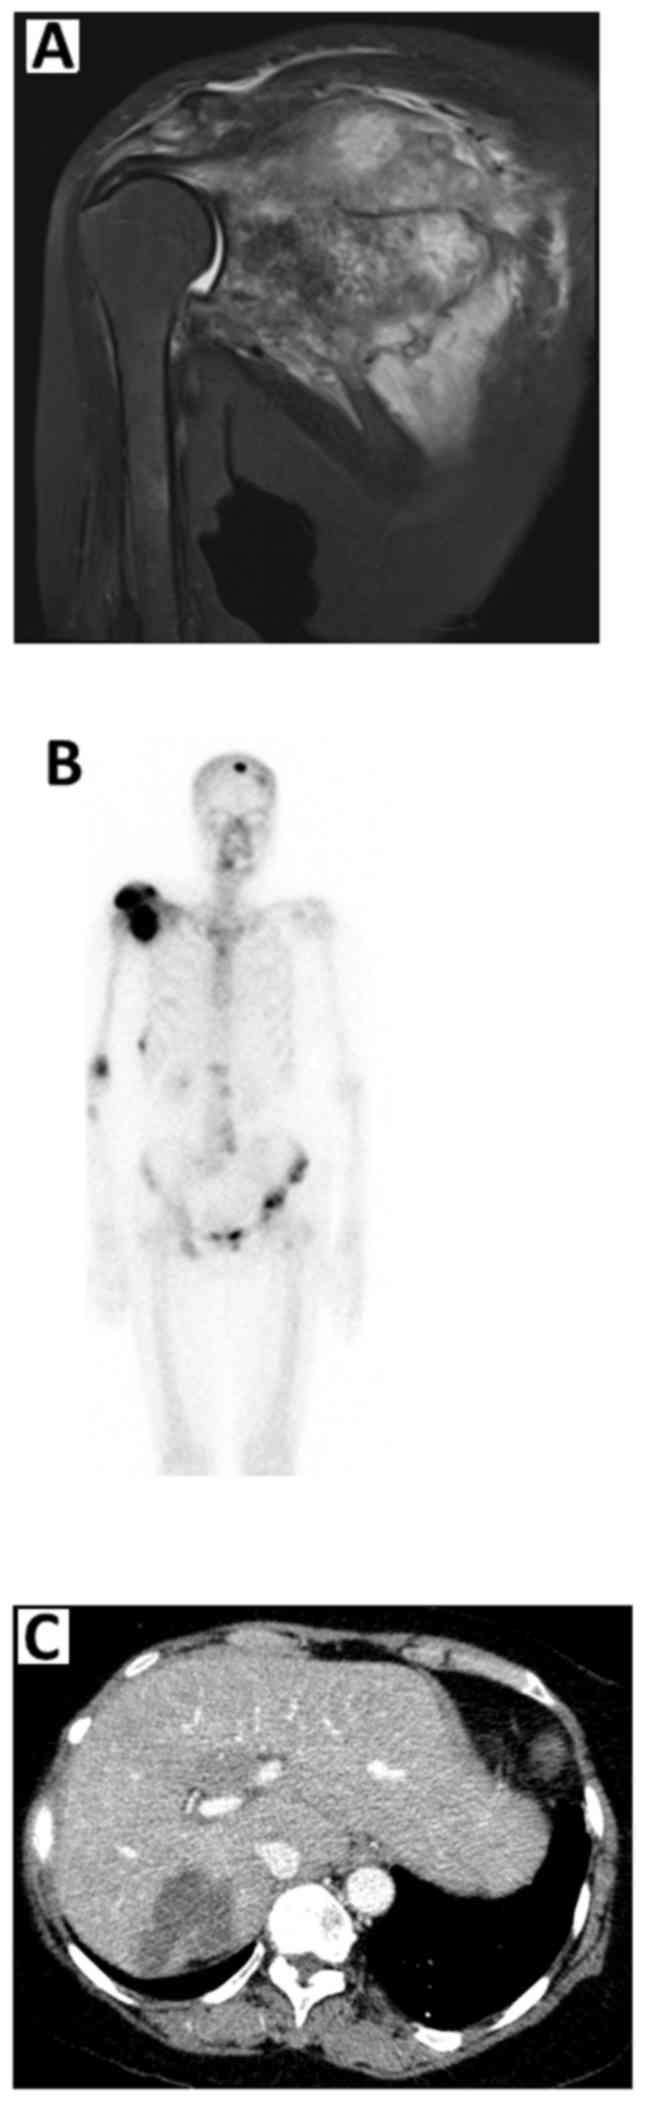

The most common symptom of bone metastases, and usually the first to happen, is pain in the bone. While bone mets are most commonly found in the spine, ribs, pelvis, long bones of the arms or legs and the skull, it is possible to find bone mets in unexpected places such. Fractures of the lesser trochanter in adults should be considered pathologic until proven otherwise.

Bone mets in rib (5 cm) and pelvis were detected in early 2018 going into year eight of cancer. Lymphoma femur, tibia, humerus, iliac bone, vertebra. Your description of your symptoms and medical history are an important part of diagnosing metastatic bone cancer. In rib fracture pain is localized over a limited area, careful displacement of bone fractures attends by a specific sound (crunch).